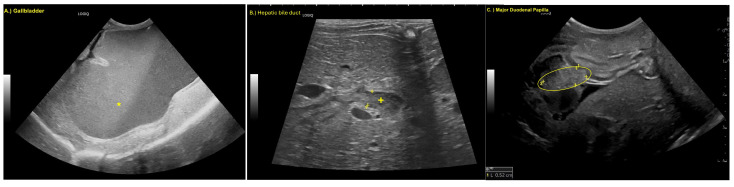

Findings were overall unchanged to mildly progressive, with the additional observation of a thickened major duodenal papilla (Figure 2).